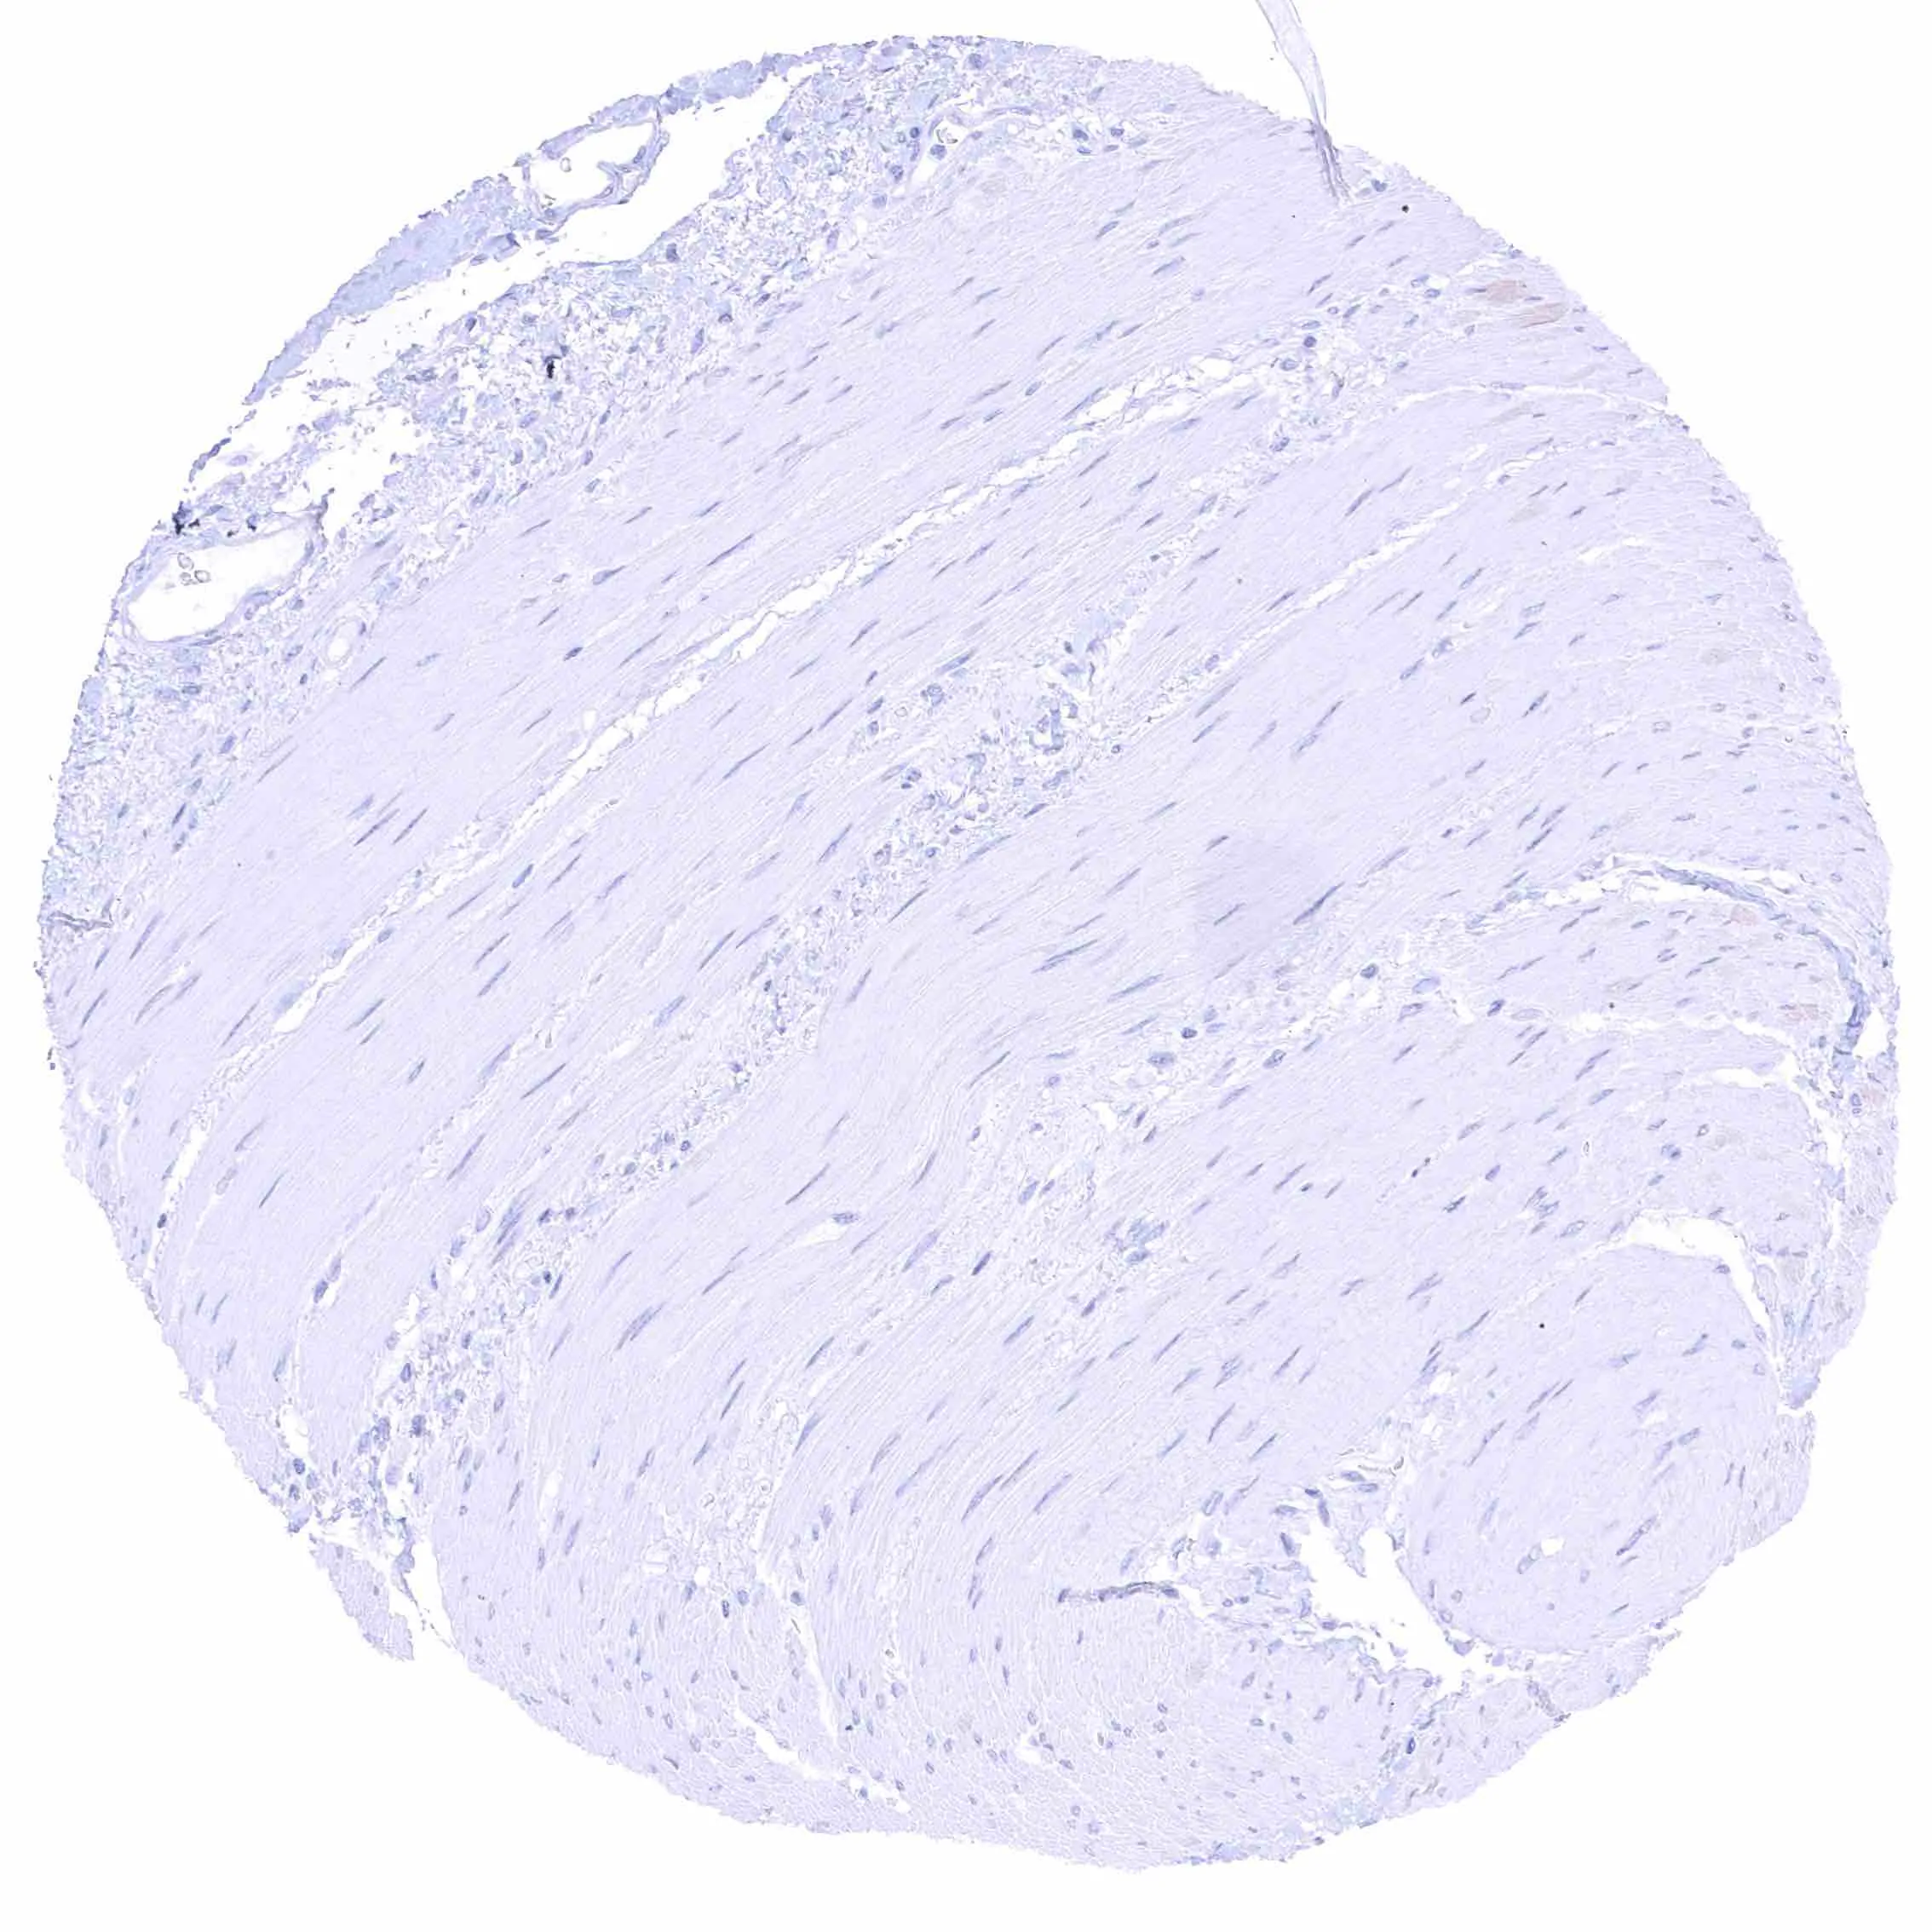

Aorta, media